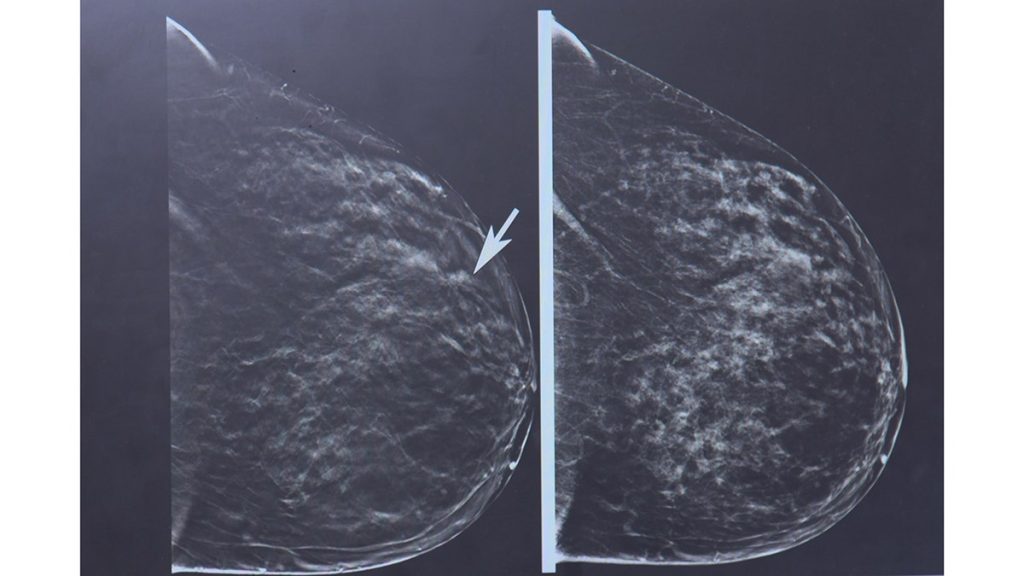

This is how lobular breast cancer can appear on a mammogram. Arya Roy, M.D., noted the cloudiness in the imaging, which would prompt her to recommend additional scans. (The Ohio State University)

Instead of a clump of cells that form a tumor, lobular cancer grows as a long chain of cells, so it shows up as a “subtle thickness” on mammograms. This means it can be difficult to spot until it has spread to other parts of the body, according to OSU.